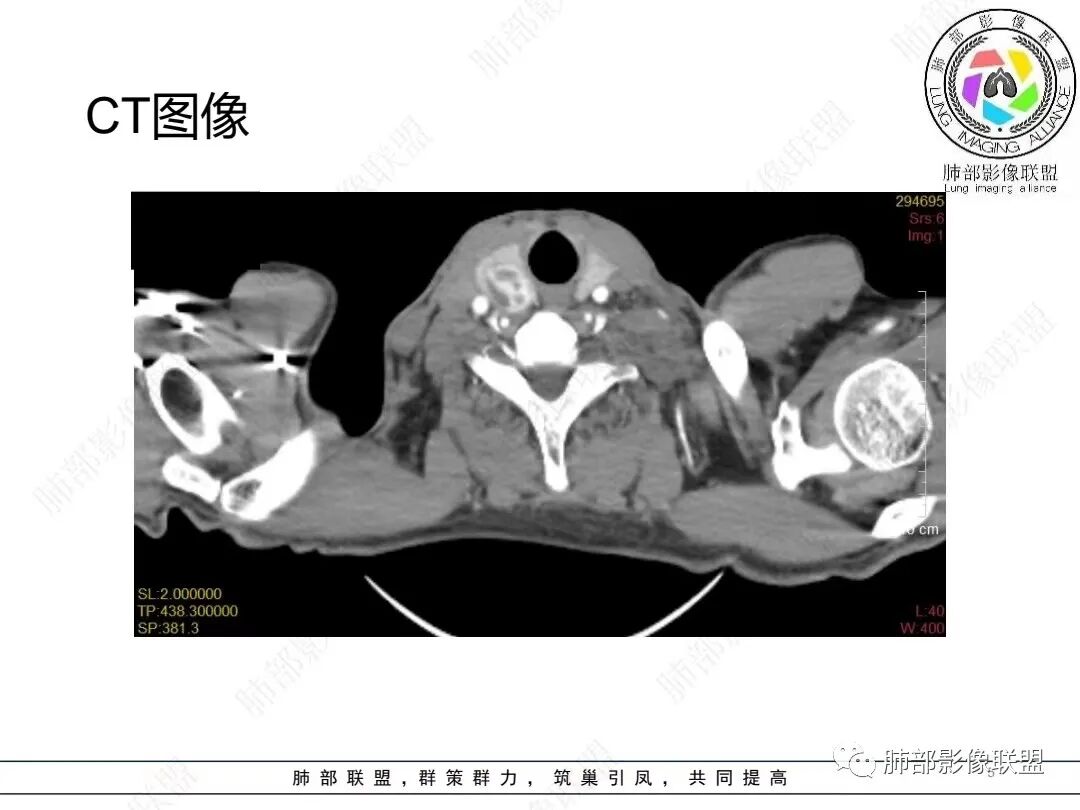

男,52,胸闷、气短、咳嗽1月。长期吸烟,NSE、细胞角蛋白19片段增高。胸部CT:甲状腺右叶结节,增强可见多发低密度区。纵隔、肺门多发淋巴结肿大融合,周围脂肪间隙消失,冰冻纵隔;针孔状食管;两侧胸腔积液伴肺不张,左侧重,胸水清澈。考虑恶性,SCLC?鉴别淋巴瘤、转移瘤等。

左侧锁骨上下及纵膈多发淋巴结肿大,左侧胸膜呈环周型增厚,左侧胸腔大量积液半肺不张,右侧胸腔少量积液,甲状腺右叶结节,中年男性,胸闷气短咳嗽,长期吸烟,NSE、细胞角蛋白19片段增高。考虑恶性,小细胞肺癌,鉴别淋巴瘤

2.影像学特点:病变范围相当广泛,多发块状影累及纵隔、胸膜、前胸壁(胸大肌下)、前上腹壁等。胸膜弥漫性斑状增厚为主,明显强化,纵隔旁椭圆形块影较密实,沿胸膜分布趋势,未见支气管等结构进入。后纵隔块影较大,占位效应明显,肺静脉受累狭窄。双侧胸腔积液。

甲状腺右叶相对低密度结节影,边界清楚,不均匀分隔样强化,经验上分析与胸部病灶缺乏关联性。